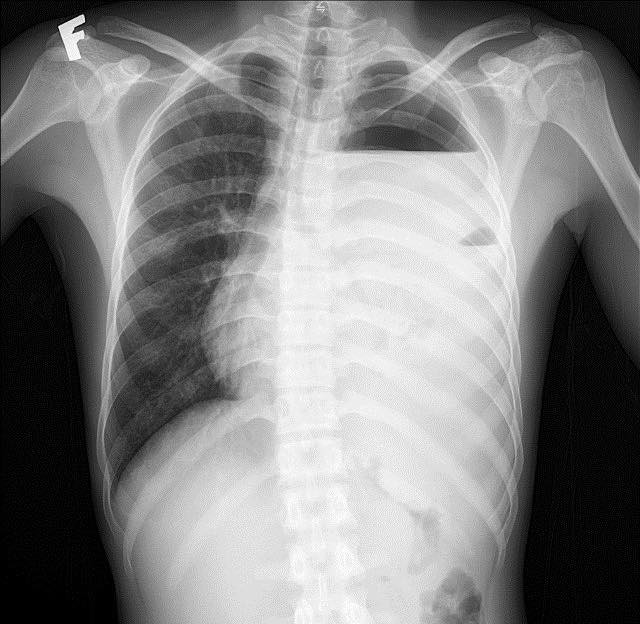

Bệnh nhân nam (20 tuổi) nhập viện trong tình trạng đau ngực trái kèm khó thở đã kéo dài 1 tuần. Qua thăm khám lâm sàng, bệnh nhân có biểu hiện vẻ mặt nhiễm trùng , SpO2 94%, mạch nhanh 130 lần/phút, huyết áp thấp 90/60 mmHg.

Hình ảnh phổi tổn thương trên phim chụp - Ảnh BVCC

Kết quả xét nghiệm máu cho thấy tình trạng nhiễm trùng nặng với chỉ số bạch cầu (WBC) lên tới 64.8 G/L, chỉ số CRP cao 263.6 mg/dL. Với hệ thống chẩn đoán hình ảnh hiện đại, các bác sĩ ghi nhận: Đông đặc nhu mô thùy dưới phổi trái, tràn dịch màng phổi trái lượng nhiều, tràn khí màng phổi trái, phổi trái bị xẹp thụ động, đẩy lệch trung thất sang phải.

Các bác sĩ khoa Ngoại Tổng hợp đã nhanh chóng đưa ra chẩn đoán: "Viêm phổi màng phổi trái biến chứng tràn mủ màng phổi" và chỉ định can thiệp ngoại khoa cấp cứu.